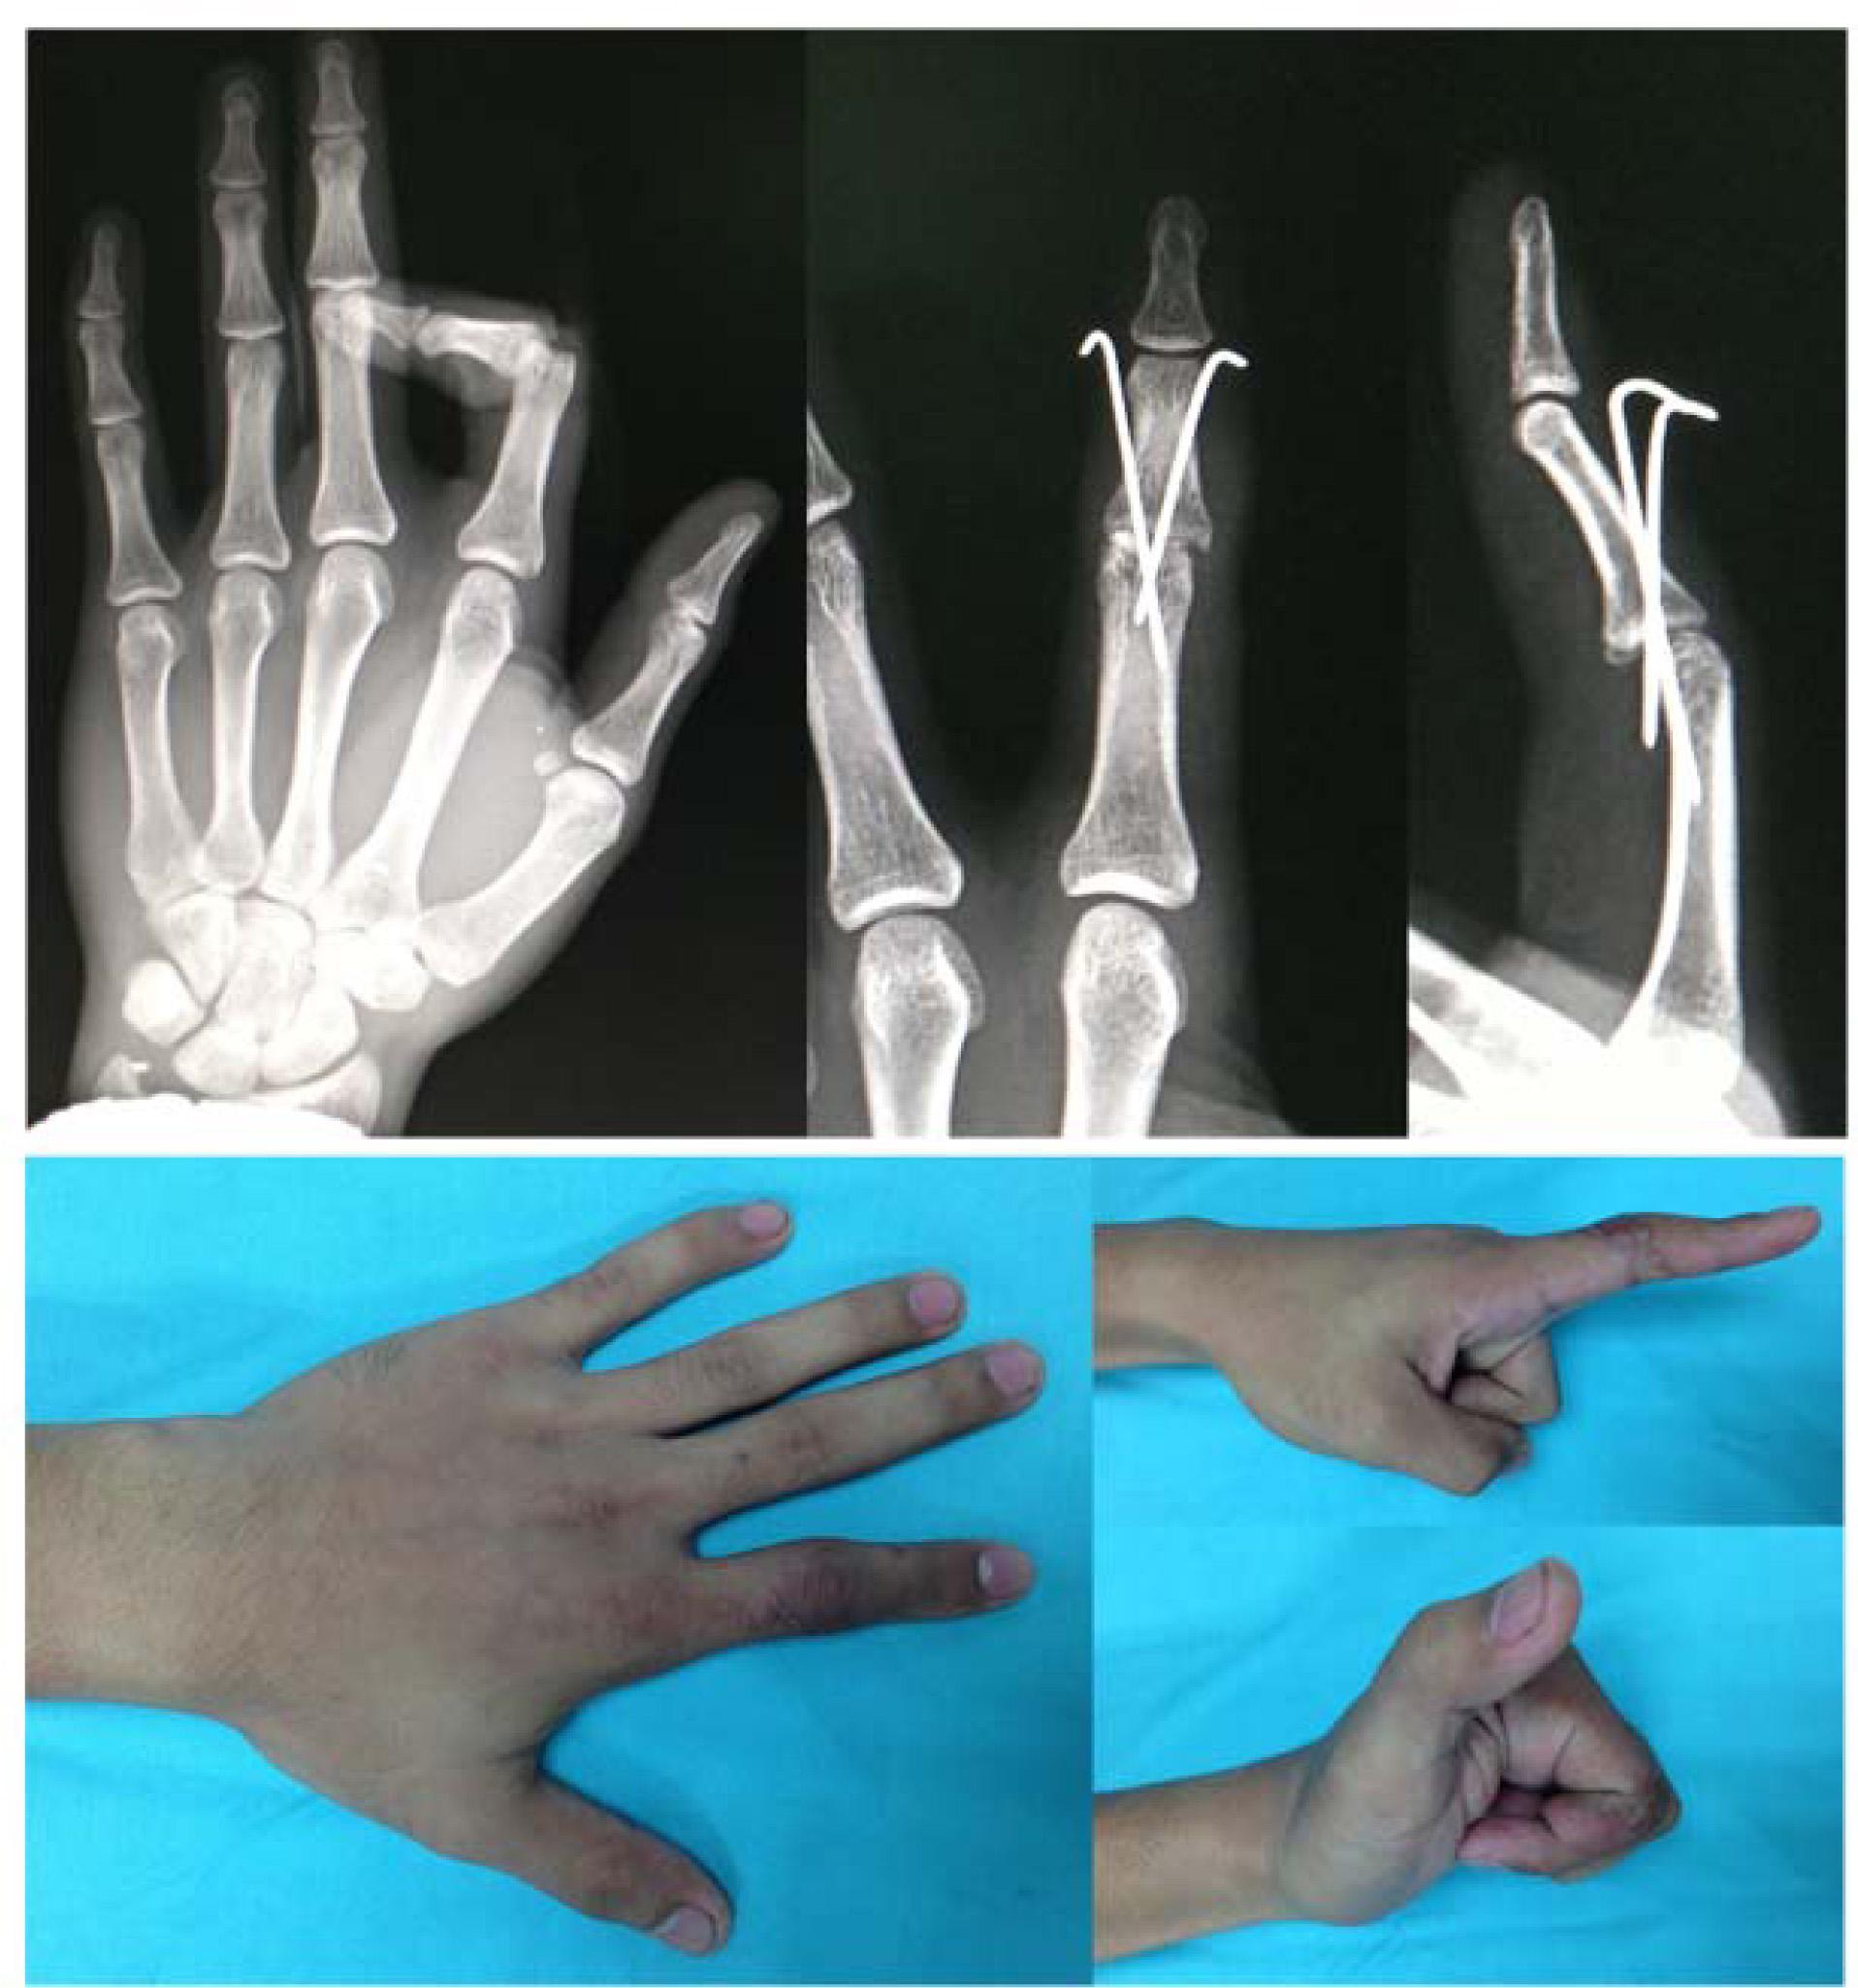

Figure 3

A 32-year-old man with PIPJ fracture dislocation, after 3 weeks K-wire fixation and a repaired index RCL. The improvised mobile frames were applied for 4 weeks. He could flex and extend his PIPJ with radioulnar protection. The range of motion after treatment was 0-120° with good radioulnar stability.